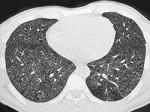

女,25岁,养鸽,咳嗽,咳痰,结合CT图像,最可能的诊断是 ( )A.肺泡癌B.肺结核C.肺隐球菌病D.支气管肺炎E.肺曲菌病